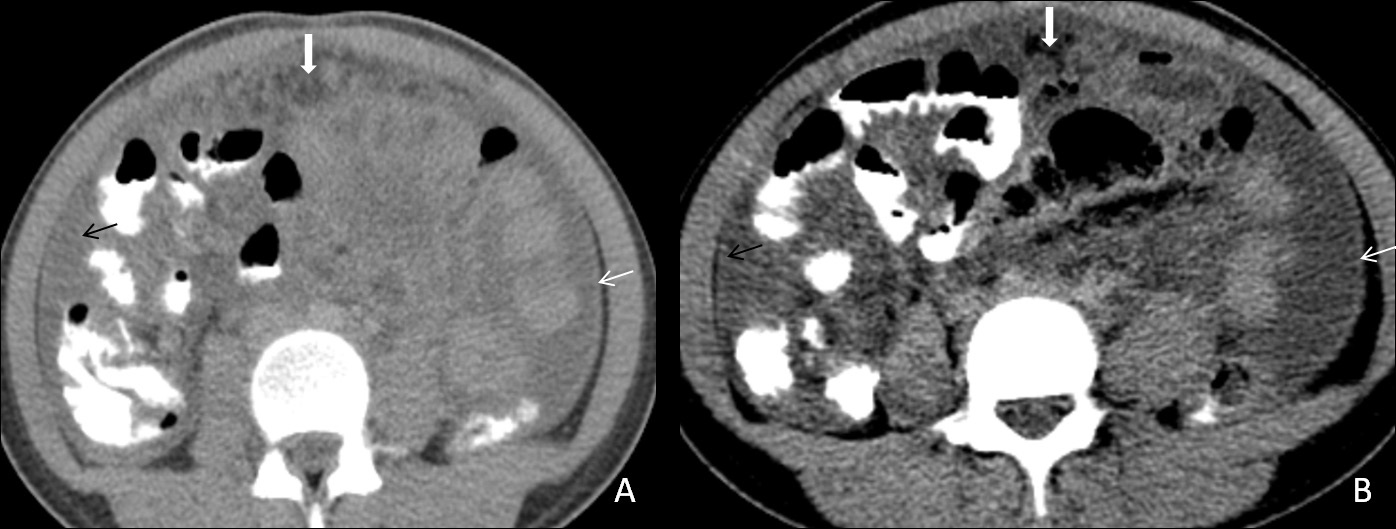

Tubercular lymphadenitis

Lymphadenopathy is the commonest finding associated with abdominal tuberculosis. A wide range of patterns can be seen, including an increase in the number of lymph nodes to large nodal masses. The commonly involved lymph nodes groups are omental, mesenteric, celiac, portahepatis and peripancreatic. The conglomerated pattern of lymph nodes is commonly seen in abdominal tuberculosis. In contrast, CT features of involved lymph nodes may vary from peripherally enhancing lymph nodes with low-density centres (signifies caseous necrosis) to homogeneous/heterogeneous enhancement. Lymph nodes calcification is also seen in chronic tubercular infection (Figure 1A,1B). The necrotic lymph nodes are not pathognomic for tuberculosis as they can also be seen in metastasis, lymphoma or Whipple’s disease [4].

Figure 1: (A) A 30 years old male patient came with a complaint of vague pain abdomen, low-grade fever and a history of significant weight loss in the recent past. On physical examination, there was diffuse pain in the abdomen without any organomegaly. Postcontrast computed tomography image from a venous phase in the axial plane illustrates multiple, conglomerated, peripherally enhancing para-aortic (white arrow) & mesenteric (black arrow) lymph nodes with central necrosis. (B) In another 60 years old male patient with similar complaints, a post-contrast computed tomography image from a venous phase in the axial plane shows heterogeneously enhancing, enlarged, and conglomerated lymph node masses with internal low attenuating areas and punctate calcification (thick white arrow) in the left para-aortic region. Both these patients were diagnosed with TB on CT guided lymph node FNAC and anti-tubercular therapy was started. Patients are now symptomatically better and kept on follow up.